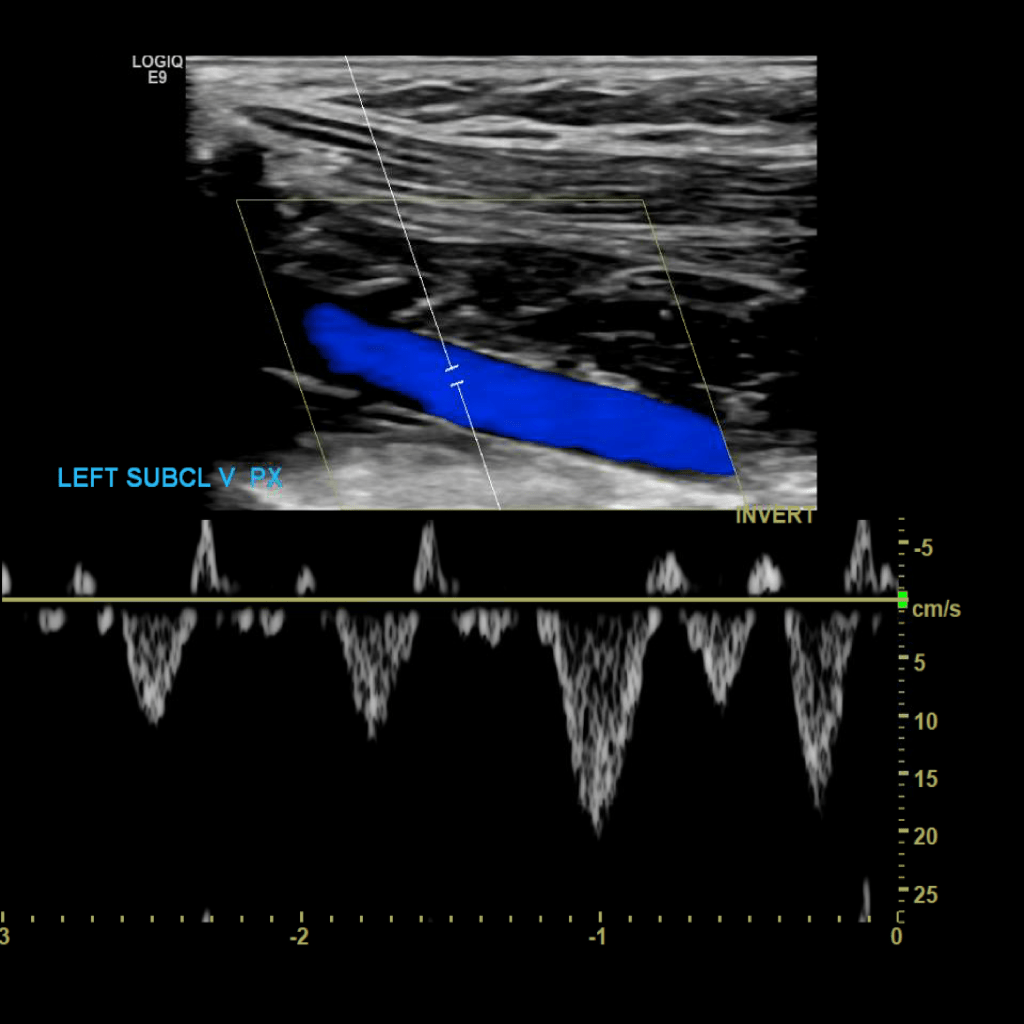

Scan the subclavian vein in grey scale, color doppler and spectral doppler